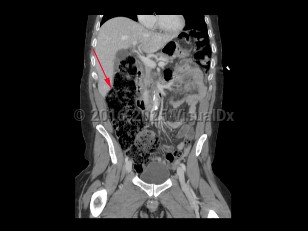

A large bowel obstruction (LBO) occurs when intraluminal contents fail to pass through the large intestine. This results in dilation of the proximal large bowel, with fluid accumulation, gas production, increased intraluminal pressure, and bacterial overgrowth. Bacterial translocation can then lead to bacteremia and sepsis.

Unlike small bowel obstructions (SBOs), LBOs often occur secondary to colorectal malignancies, accounting for 60% of all cases. Stenosis secondary to diverticular disease and volvulus account for another 30%. Other causes include compression from intra-abdominal masses and stenosis secondary to inflammatory bowel disease, radiation, or surgical anastomoses.

LBOs may be partial or complete. A simple LBO is characterized by a single point of obstruction. A closed-loop obstruction is characterized by occlusion of the bowel at 2 points and has the highest risk of ischemia due to occlusion of the blood supply. A classic example of this is sigmoid volvulus. A competent ileocecal valve may also contribute to closed loop obstructions as the large bowel cannot decompress proximally.